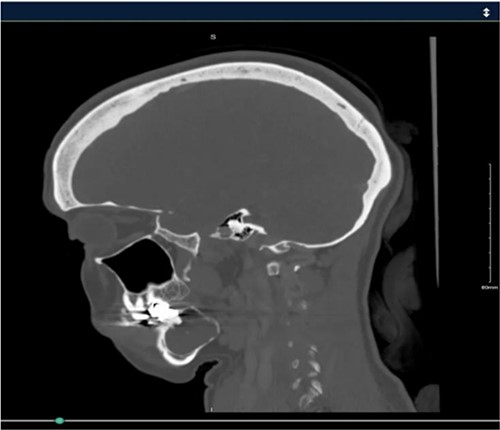

A 40-year-old woman presented with swelling on the right side of her mandible. She had completed orthodontic treatment 2 years earlier. A panoramic radiograph showed a unilocular radiolucency extending from the mandibular angle to the right first molar region (Figs 1–3).

Panoramic radiograph highlighting the extent of the lesion from the mandibular angle to tooth #46.